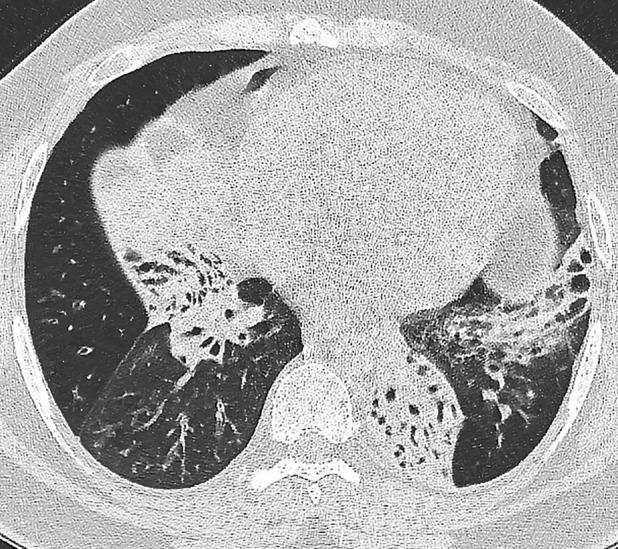

Hypertrophic pulmonary osteoarthropathy (HPOA) is a well-documented complication of pulmonary malignancy and cystic fibrosis (CF). However, HPOA associated with exacerbations of non-CF bronchiectasis has only been reported once previously in an adolescent. We describe a case of an adult patient with bronchiectasis and HPOA, whose joint symptoms flared during pulmonary exacerbations and improved with treatment of each exacerbation.

肥厚性肺骨关节病(HPOA)是一种已被充分记录的肺部恶性肿瘤和囊性纤维化(CF)的并发症。然而,与非CF支气管扩张症加重相关的HPOA此前仅在一名青少年中报道过一次。我们描述了一例患有支气管扩张症和HPOA的成年患者,其关节症状在肺部病情加重期间发作,并在每次病情加重得到治疗后有所改善。